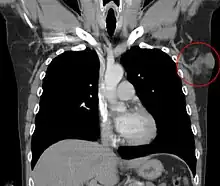

Clinical palpation is not entirely reliable for ascertaining the depth of a DFSP infiltration. Magnetic resonance imaging (MRI) is more sensitive addressing the depth of the invasion on some types of DFSP, particularly large or recurring tumors.[20][21] Though MRI is less accurate for identifying infiltration to head and neck tumors.

Metastases to regional lymph nodes are extremely rare.[33] Distant hematogenous metastases are even rarer and are most likely in patients who have had multiple local recurrences after inadequate surgical resection.[34] Repeatedly recurring tumors have an increased risk for transformation into a more malignant form (DFSP-FS). The lungs are most frequently affected, but metastases to the brain,[35] bone,[36] and other soft tissues are reported.